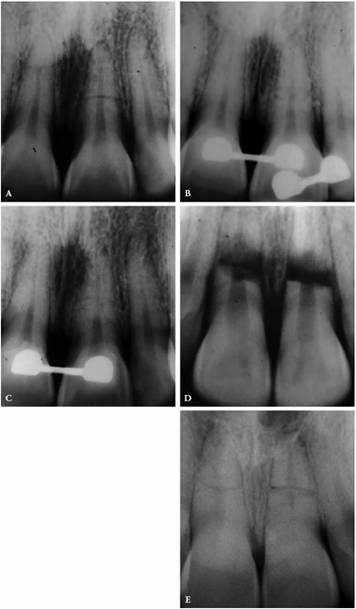

One can suspect a necrotic pulp if the reading is negative. Endodontics would

then be the treatment of choice (Figures 19-17A, and 19-17B). If the reading is positive and

there are no pulpal symptoms, periodontal therapy would be indicated (Figures 19-17C 19-17D, and 19-17E). Endodontic treatment may be

required if the root apices are compromised during periodontal procedures (Figures 19-17F, and 19-17G

Figure 19-17A: Mandibular molar with a necrotic pulp. Root canal therapy was instituted.

Figure 19-17B: Ten years following completion of root canal therapy there is a complete bone fill-in. No periodontal treatments were performed on this tooth.

Figure 19-17C: Maxillary central incisor tooth with a vital pulp. Endodontic therapy was not indicated.

Figure 19-17D: A maxillary first molar with a periapical radiolucency.

Figure 19-17E: A gutta-percha point placed in the distal pocket. Pulp testing through an occlusal opening revealed a vital pulp. The cause of the radiolucency was of periodontal origin and therapy followed that course.

Figure 19-17F: Maxillary first molar with an uninflamed vital pulp. There was extensive bone loss surrounding the distobuccal root.

Figure 19-17G: Root canal therapy was performed to allow for the resection of the periodontally involved root.